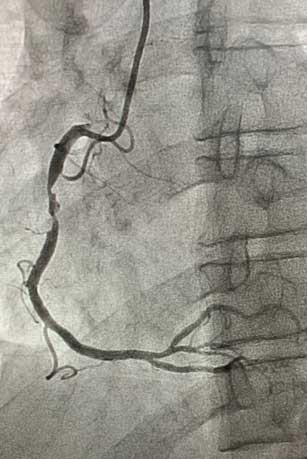

患者为45岁男性,因间断发作剑突下疼痛10天就诊于我院心血管内科门诊,完善检查后以“冠心病、不稳定型心绞痛”收入心血管内科病房。冠脉造影示:右冠近中段90%节段性狭窄,与冠脉CTA诊断一致。患者右冠状动脉近中段存在重度狭窄病变,有植入冠脉支架指征。心血管内科介入团队在赵慧强主任的带领下,针对此患者制定了个体化介入治疗方案:患者的病变特点为右冠状动脉近中段病变,无严重钙化、迂曲,非左主干病变、分叉病变、小血管病变,且患者年龄较轻,综合考虑远期预后效果,此患者适用于植入生物可吸收支架。冠脉介入团队进行了详细的术前讨论和充分的准备,经过患者同意后,为其行生物可吸收支架植入术。术中,经过充分预扩张处理右冠状动脉近中段狭窄病变后,成功于右冠状动脉病变处植入一枚生物可吸收支架。术后即刻复查冠脉造影:右冠状动脉中段支架膨胀贴壁良好,手术成功。

生物可吸收支架植入术前.jpg术前